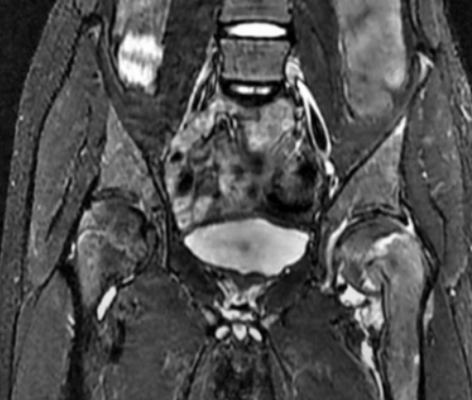

МРТ костей таза что показывает

Таз - часть скелета человека, обеспечивает прикрепление к туловищу нижних конечностей, является опорой и вместилищем для органов. Симптомы патологических процессов в указанной зоне, вне зависимости от природы, схожи. МРТ костей таза - ведущее исследование для выявления причины заболеваний костно-мышечной системы.

Магнитно-резонансная томография демонстрирует подвздошную, лобковую, седалищную кости, симфиз (спереди) и копчик (сзади), тазобедренные суставы, внутренние органы (мочевой пузырь, простату, матку, часть кишечника и пр.)

Заболевания костей малого таза

МРТ-признаки остеомиелита лонных костей: расширение сочленения и скопление жидкости с формированием параартикулярных затеков (длинные стрелки), разрастание грануляционной ткани (короткие стрелки), Т2-ВИ, аксиальная (а) и коронарная (в) плоскости

Магнитно-резонансное сканирование нашло применение в травматологической, ортопедической, ревматологической, онкологической практиках, так как генез патологических процессов многообразен. Исследования проводят для диагностики причин острой и хронической боли.

Что покажет МРТ костей таза:

- отек, присутствие инородного тела, крови, больших скоплений жидкости;

- повреждения крупных мышц и сухожилий при травматизации, перелом костей таза, в том числе, с разрывом кольца;

- дегенеративные изменения в суставах с разрушением хрящевой ткани (остеопороз) и аваскулярный некроз тазобедренных сочленений (видны на бесконтрастной МРТ);

- расхождение лонных костей (симфизиолиз), гипоплазию таза (недоразвитие, врожденный синостоз), дисплазию бедра или врожденный вывих и пр.;

- атрофию мышц, окружающих сустав;

- синдром отека костного мозга;

- туберкулезное, сифилитическое поражение (окончательная диагностика требует проведения специальных тестов);

- защемление нервных окончаний;

- остеохондропатию головки бедренной кости (болезнь Пертеса);

- наличие обширных участков воспаления, дегенеративные процессы в сухожилиях (тендинит), синовиальной сумке (бурсит), суставах (артрит, артроз, спондилез) и пр.;

- неопластические процессы: остео-, хондро-, фибросаркому, гистиоцитому, костные метастазы, поражение лимфатических узлов;

- повреждения апофиза, стрессовые переломы таза, шейки, диафиза бедренной кости и пр.;

- анкилозирующий спондилит крестцово-подвздошных сочленений (болезнь Бехтерева);

- внутрисуставные разрывы губ (диагностируют с помощью магнитно-резонансной артрограммы, подразумевающей введение контраста в тазобедренный сустав под контролем ультразвука) и др.;

- неполноценную конфигурацию вертлужной впадины;

- плексит пояснично-крестцового сочленения;